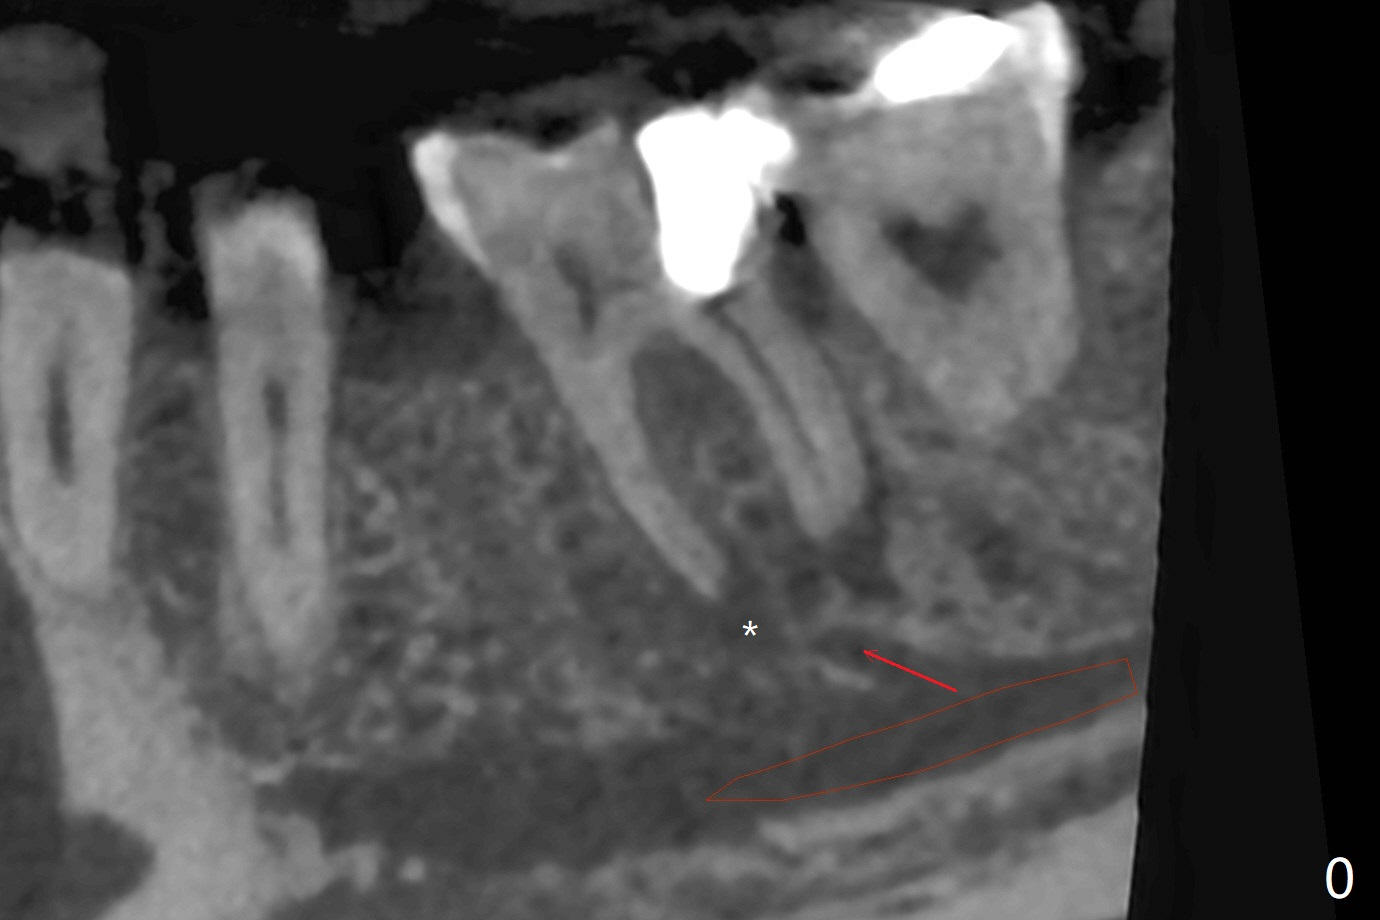

35岁男牙齿矫正后2年5个月右下6远中深龋,拔除后,近中根尖肉芽组织(图零(术前CT冠状切面):*)刮除疼痛,必须阻滞麻醉才能控制疼痛,可能与下牙槽神经分支(图零:红箭头)有关。原先准备在近中牙槽窝近中种植(5x11.5mm),术中发现近中牙槽窝种植好像方便,位置不错,不由自主在那里开始钻洞,由于牙槽窝深,钻洞必须13毫米(图一(接近神经:红虚线)),之后发现钻洞(图二(术前CT3D长轴切面(黑色:近中,远中牙槽窝)):红圆圈)不够理想,使用Lindamann Bur将钻洞往颊侧近中移动(图二:箭头),最终在这方面结果可以(图三,三’,四),虽然接近神经,术后没有神经麻痹。放置粘性骨粉(图四:*),PRF膜,4-0 PGA缝线(图五),最后使用树脂敷料(图六:A)。后牙垂直空间少,术后一周需要降低树脂敷料高度(图七)。术后一个月取出敷料,牙槽窝愈合,植体平台远中稍微暴露(图八),准备一个月后制作临时牙冠。术后两个月植体远中没有暴露,但是基台远中边缘太高了(图九:>),换成6x4毫米愈合基台。下个月换成袖短的修复性基台,安置临时牙冠,牵拉7。舌侧cleats之间放置power chains,颊侧power hooks。其实术后4个月安置临时牙冠和band(图十),牙冠牙合面加高,这样7可以无阻挡移动(图十一:*;16x22 arch wire)。7远中放置power hook行不通,因为末端碰到颊侧前庭牙龈,造成创伤。只好用7颊侧原有牵引勾,在6近中安置一个短的power post (? 图十:箭头),按常规post往下,之间放置12毫米closed spring。如果post往上安置,7牙根牵引可能更有效?近中牵引一个月,第二磨牙前移大约2毫米(图十二:^),稍微近中倾斜,closed spring从12毫米更换到9毫米,舌侧换新的power chains x 4。下一个预约,用sensor 1拍摄根尖片证实第二磨牙近中倾斜,然后在它远中16x22钢丝安放power hook,下缘向颊侧弯曲,避免接触接触粘膜。